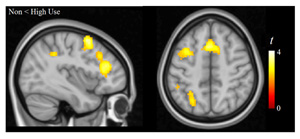

“En l’anàlisi de les imatges de ressonància magnètica del cervell d'un subgrup de nens de l’estudi, es va observar que l’ús dels videojocs estava associat a un millor funcionament de circuits cerebrals que són importants en l'adquisició de noves habilitats a través de la pràctica, concretament de les connexions entre els ganglis basals i els lòbuls frontals” explica el Dr. Pujol.

Imatges de ressonància magnètica de les connexions funcionals entre els ganglis basals i els lòbuls frontals (part superior esquerra), connexions molt importants en l'adquisició de noves habilitats a través de la pràctica. L’ús dels videojocs està associat a un millor funcionament d’aquestes connexions, tal i com mostra el gràfic (part superior dreta) i la comparació entre nens que no jugaven i els que jugaven més (part inferior).